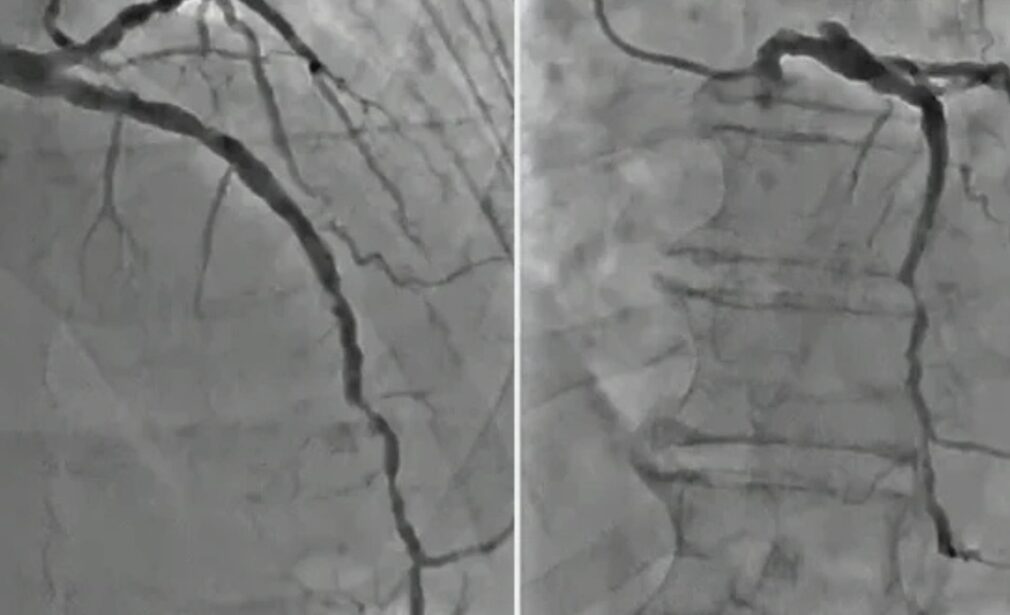

Coronary Angiography (CAG)

Intravascular Ultrasound (IVUS) – Provides high-resolution artery imaging

Optical Coherence Tomography (OCT) – Enables detailed stent placement precision

Techniques used for Left Main/Bifurcation PCI include:

Provisional Stenting – Stenting the main branch first, followed by the side branch if needed

Double Stenting Techniques – Including Culotte, DK-Crush, and T-Stenting for complete coverage